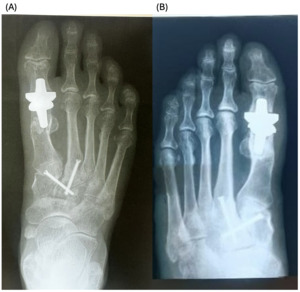

The patients had undergone radiographic evaluation of the MTP joint before the surgery, right after surgery, and 2 and 6 months after surgery (Figures 4-9). The radiographic imaging after the surgery confirmed the correct positioning and alignment. At the follow-up, the radiographic images were done to analyze the early healing process, to observe if there were any signs of implant loosening. 2 months after the surgery, no patient had periprosthetic radiolucencies, no stress-related changes. 6 months after surgery, no osteolysis, no migration of the implant.

._patient_c__immediate_postoperative_radiograph_(b).png)

._patient_c__6-month_follow-up_radiograph_(b).png)